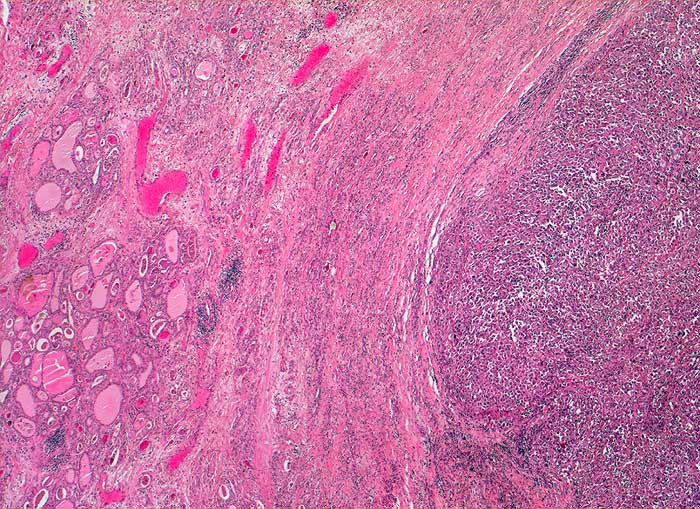

Abstriche von anaplastischen Karzinomen sind gewöhnlich sehr zellreich ausser bei ausgeprägter Desmoplasie. Die Grösse und die Form der Tumorzellen ist äusserst variabel. Oft finden sich sehr grosse, bizarre und spindelförmige Zellen. Die Kerne weisen offensichtliche Zeichen der Malignität auf: irreguläre Kernmembran, grobes dunkles Chromatin und Makronukleolen. Mitosen, auch atypische, sind häufig. Das Zytoplasma variiert von blass und vakuolisiert über granulär bis dicht. Nekrosen, neutrophile Granulozyten und eine Tumordiathese im Hintergrund sind typisch. Die Tumoren exprimieren Vimentin und Zytokeratine, sind aber negativ für Thyreoglobulin und TTF1 (Thyroid Transcription Factor).